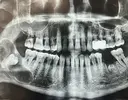

Implant tedavisi